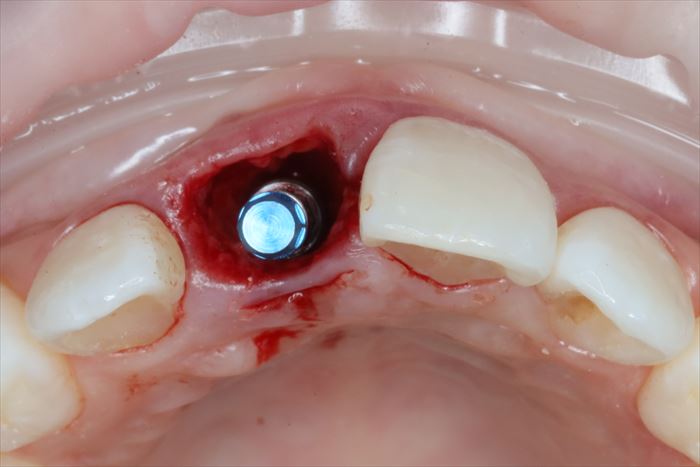

ここからはドリリングを行い、インプラントを植えるためのインプラント床(しょう)を形成します。

深度ゲージを挿入して角度・深さを確認している場面です。

_

歯根の先端があった部分よりも口蓋側にインプラントの先端が位置するように、

明確な意思をもってドリリングする必要があります。

その面では抜歯即時埋入インプラントオペは難易度の高いオペといえます。

インプラントの埋入を終えました。

深さ・角度・埋入トルクを調整しながら埋入します。

全て同等に最重要項目ですので納得出来るまでしっかりと調整します。

インプラント埋入用の挿入ジグを外しました。

前歯のインプラントの失敗の原因として、唇側すぎる位置付けミスがあります。

歯根があった場所にそのまま植えると唇側すぎる位置付けになりがちですので注意が必要です。